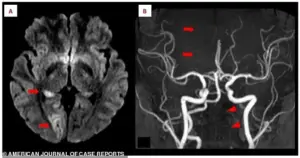

MRI scans painted a clear picture of the crisis.

Panel A revealed bright white spots in the right occipital lobe, a region critical for vision.

These bright signals, called hyperintensities, indicated a lack of blood flow due to the stroke.

Panel B showed a missing section of the right posterior cerebral artery, a key blood vessel, confirming the blockage.

Lower arrows on the same scan pointed to the left vertebral artery in her neck, which appeared faint or broken. “This artery is like the lifeline to the brain,” explained Dr.

Martinez. “When it’s compromised, the brain is starved of oxygen, and that’s when the damage begins.”